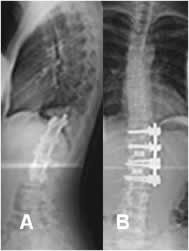

Fig 41. Corrección quirúrgica.

A: Rx lateral y B: Rx AP. Corrección de escoliosis dorsal, mediante barras posteriores.